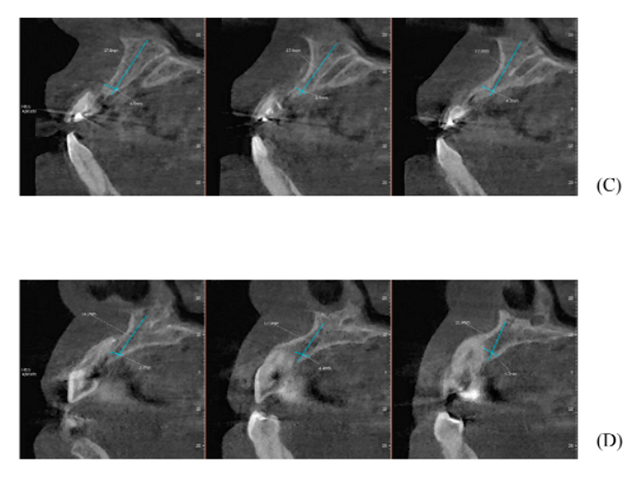

Figuras A,B,C, D e E – Imagens evidenciando grande perda óssea anterior no sentido horizontal, bem como a vestibularização do rebordo anterior, o que impossibilita a instalação dos implantes em um bom posicionamento tridimensional.

Após oito meses, foi realizada outra tomografia computadorizada (TC) na própria clínica escola, onde foram realizadas medidas de altura e espessura evidenciando grande ganho ósseo horizontal. Não ocorreu quaisquer tipo de complicação no pós-operatório tardio (imagens 1-A, 1-B, 1-C, 1-D).